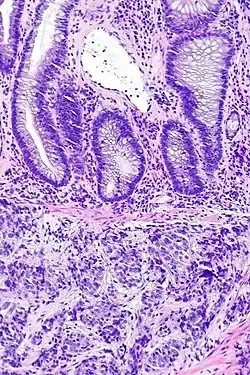

Gruczolakorak prostaty (obraz mikroskopowy, barwienie hematoksyliną i eozyną)

Gruczolakorak gruczołu krokowego, obraz mikroskopowy

W prawej górnej części preparatu obecny gruczolakorak, obok widoczne są prawidłowe gruczoły tworzące utkanie stercza

W obrazie mikroskopowym gruczolakoraki gruczołu krokowego znacznie różnią się stopniem zróżnicowania (złośliwości histologicznej), dając spektrum nowotworów od dobrze zróżnicowanych (o niskiej złośliwości), które trudno odróżnić od prawidłowego utkania gruczołu krokowego do zmian o niskim zróżnicowaniu (o wysokiej złośliwości)[155]. Cechą wspólną dla wszystkich raków stercza jest obecność pojedynczej warstwy jednego typu komórek bez warstwy podstawnej, która jest widoczna w prawidłowych cewkach gruczołowych[156][152].

W dobrze zróżnicowanych nowotworach komórki nowotworowe tworzą stłoczone cewki gruczołowe o nieregularnym kształcie i różnej wielkości, które są wyścielone przez jedną warstwę komórek. Cewki gruczołowe są ułożone w dość bezładny sposób[156]. Kolejnym wzorem utkania typowym dla nacieku jest obecność atypowych struktur gruczołowych między dużymi, prawidłowymi gruczołami. Wraz z utratą różnicowania i tworzeniem struktur sitowatych, połączonych gruczołów lub słabo uformowanych gruczołów, coraz bardziej zaznacza się różnica między łagodnymi gruczołami a strukturami tworzonymi przez komórki nowotworowe[156]. Nisko zróżnicowane nowotwory są zbudowane z litych arkuszy lub sznurów komórek, a cewki gruczołowe są nieliczne lub poronne[156][157].

Komórki cechują się obecnością powiększonego jądra komórkowego i powiększonego jąderka. W niektórych komórkach nie jest obecne powiększone jąderko, jednak pozostają powiększone i hiperchromatyczne[158][159]. Figury mitotyczne mogą być liczne w nowotworach o wysokiej złośliwości[158]. Cytoplazma komórek budujących struktury gruczołowe jest amfifilna, w jej obrębie nie stwierdza się lipofuscyny[158].

Może być widoczna inwazja naczyń krwionośnych i chłonnych oraz nerwów, która jednoznacznie przemawia za złośliwym charakterem nowotworu[159]. Innymi cechami wskazującym na złośliwość nowotworu jest obecność struktur przypominających kłębuszki oraz niewielkich guzków zbudowanych z eozynofilnych włókien w obrębie cewek gruczołowych (mucinous fibroplasia, collagenous micronodules)[160][159]. W cewkach gruczołowych bywa obecna mucyna, ale jej obecność nie jest swoista dla raka. W guzach o niskiej złośliwości są obecne krystaloidy (prostatic crystalloids) widoczne jako ostre, gęste eozynofilne struktury o różnych kształtach geometrycznych obecne w świetle cewek, jednak ich obecność nie jest charakterystyczna dla raka[158][159].